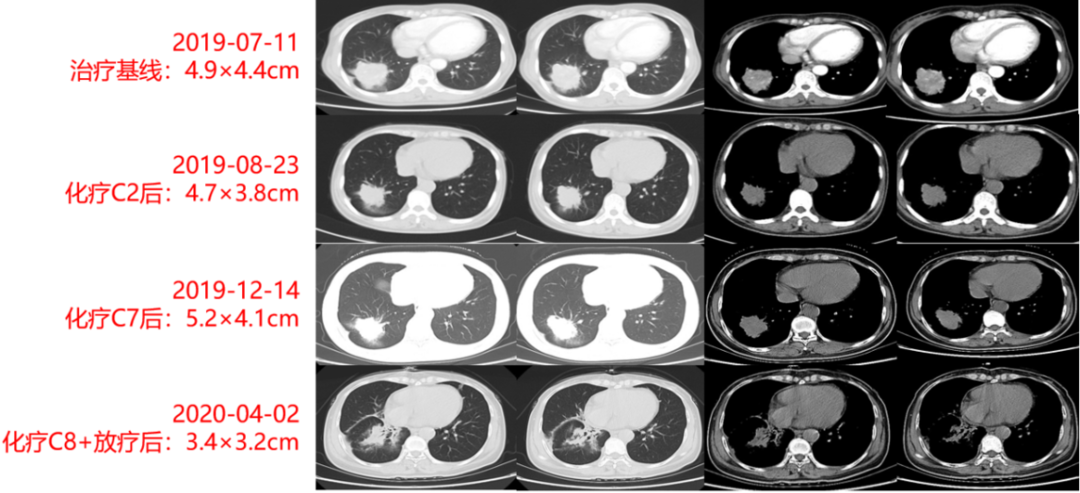

胸部CT(2019年07月11日):如图2-1所示,病灶大小约4.9×4.4cm。

图2-1:治疗基线期胸部CT

治疗方案:经胸外科、放疗科、化疗科、影像科、病理科MDT讨论后,予患者培美曲塞+卡铂方案化疗,共2周期,同时完善基因检测及免疫治疗预测等检查结果回报(见“病例一基本情况”)后,予患者调整为培美曲塞+卡铂+贝伐珠单抗方案(第3-6周期)、培美曲塞+贝伐珠单抗(第7周期)、放疗(60Gy)+培美曲塞+贝伐珠单抗(第8周期)治疗。

影像学及疗效评价:患者治疗期间定期复查胸部CT,右肺原发灶大小分别为4.7×3.8cm(2周期后)、5.2×4.1cm(7周期后)、3.4×3.2cm(8周期后,与放疗关系大),提示患者对化疗疗效差病灶变化如图2-2所示。

图2-2 治疗期间胸部CT动态变化